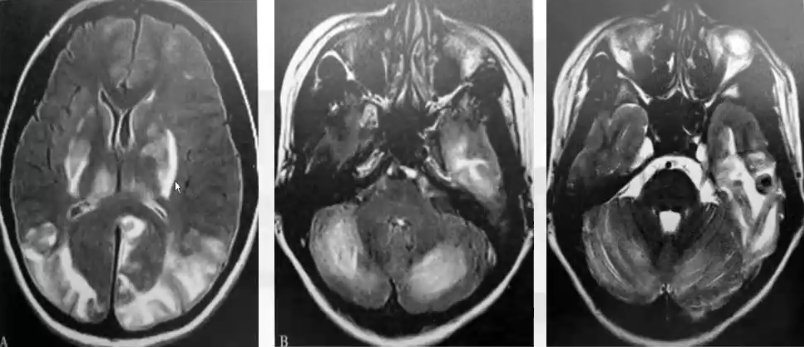

影像学改变的特点为皮质下白质脑水肿,可累及皮质,丘脑和脑干可受累。通常病变白质重于灰质,后循环重于前循环。两侧基本对称,也可不对称,占位效应轻

CT和MR的典型表现为对称性的血管源性水肿,主要出现在后循环区域。DW常为正常表现,但是部分患者也会出现弥散降低,提示细胞毒性脑水肿的出现。

女,25岁,妊娠高血压。双侧基底节-丘脑区、双侧题顶枕叶皮质及皮质下、双侧小脑半球白对称性高信号,左侧题叶可见出血。